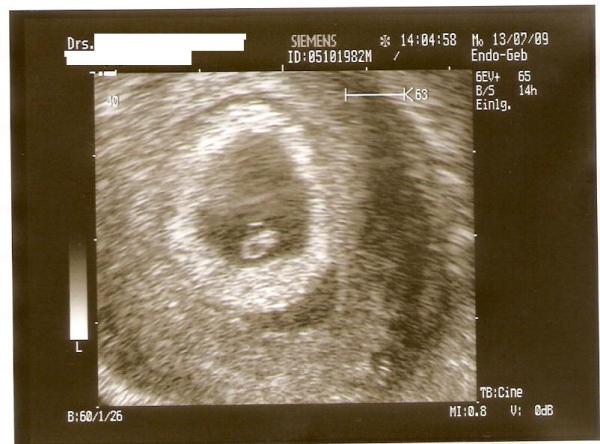

Waren gerade bei FA. Wir konnten schon das Herz schlagen sehn (aber sonst kann man noch nicht viel erkennen). Soweit alles bestens. Bin noch immer total aufgeregt :-) Meinen Mutterpass bekomm ich in ca. 2 Wochen :-)

nach meiner Rechnung 7+6. Laut Rechnung vom FA Anfang bis Mitte 7 Woche. Meine Ärztin will sich auf die Woche erst nach Erhalt vom Blutergebnis festlegen. Aber ist auch ganz egal, weil weder Sie noch ich entscheiden wann mein Baby so weit ist :-)

meinte natürlich 6+6... also 7te Woche :) Alles noch so verwirrend :)